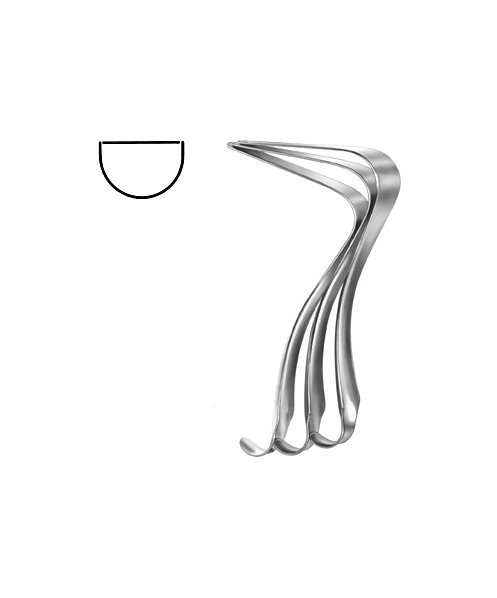

- Gynecology, Surgical Instruments

Endocervical Speculum

- Size : 34.5 CM - 13 1/2"

- Read more